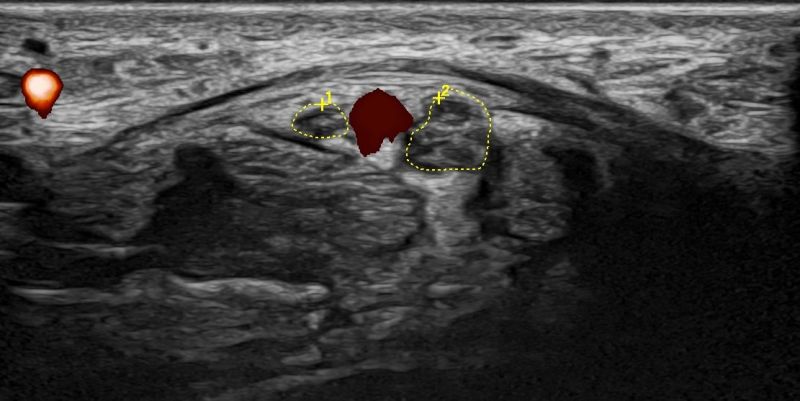

- Focal Lesions (tumors, neuromas)